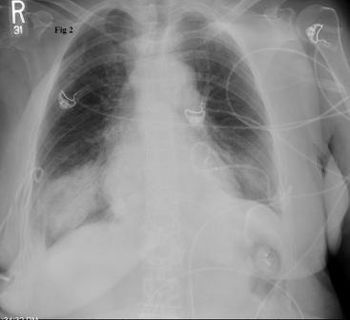

Re-expansion pulmonary edema is noncardiogenic and follows re-expansion of the lung after thoracentesis is performed for large amounts of pleural effusion or for pneumothorax.